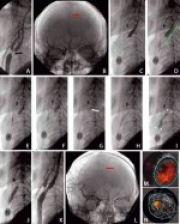

A case of bilateral persistent sciatic artery with unilateral aneurysm: An 18-year period of graft patency after excision of aneurysm

Włodzimierz Drożdż, Andrzej Urbanik

DOI: 10.12659/MSM.882454

Med Sci Monit 2012; 18(2): CS12-15

Włodzimierz Drożdż, Andrzej Urbanik, Piotr Budzyński